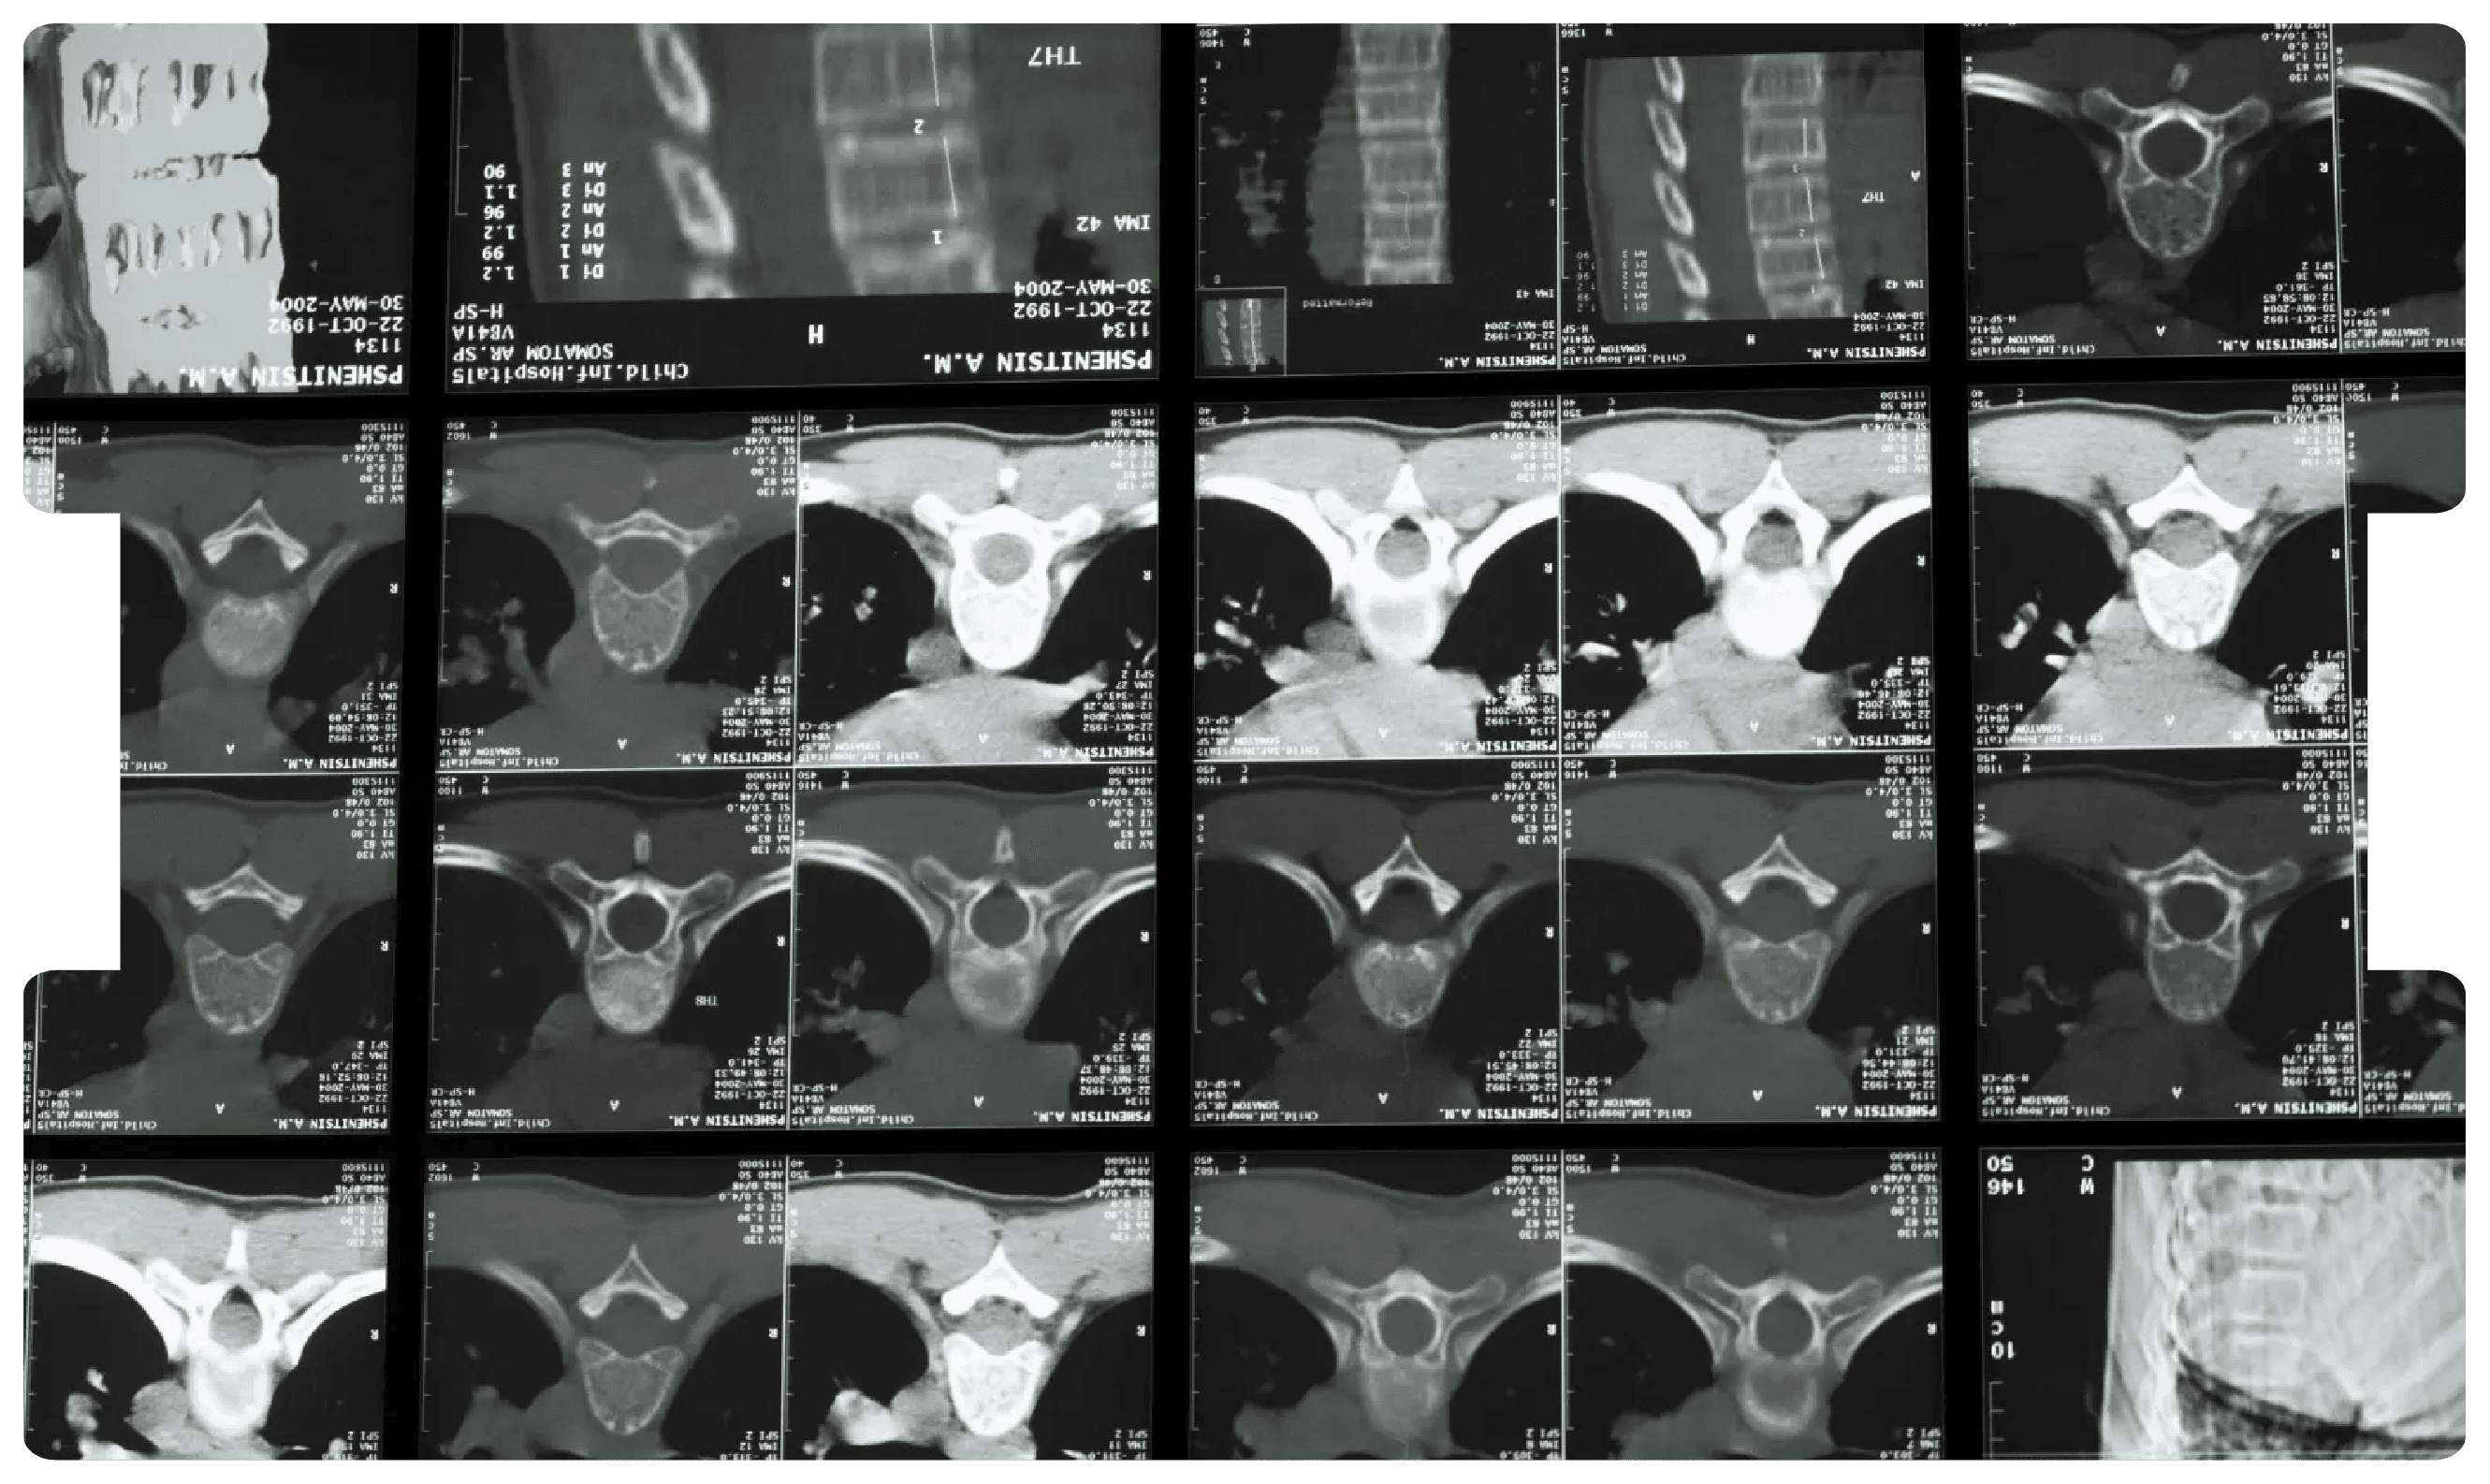

Why You Can't Replace a Face-2-Face Examination when it comes to Spinal Injury Claims

By Mr Neil Slater, Consultant Trauma, Orthopaedic, & Spinal Surgeon